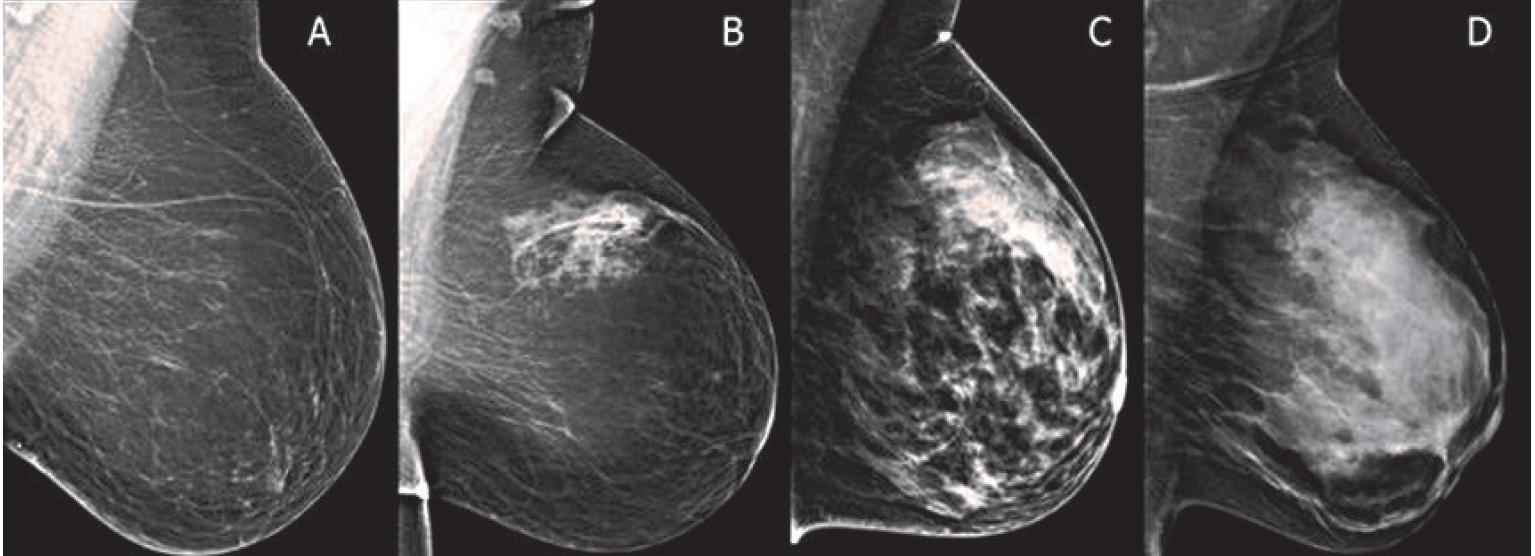

Let me explain why. Dense breasts appear more white on mammograms than non-dense breasts. But cancers usually appear white on mammograms, too. The more white the mammogram appears, the more difficult it is to detect cancer.

[Photo source: Cassling.com] Breast density from less dense (left) to higher density (right).